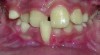

The American Association of Orthodontists recommends an orthodontic screening by age 7, or even earlier if a parent or a dentist discerns a problem.1 By this age, several permanent teeth in most children have erupted, allowing the orthodontist to effectively evaluate the orthodontic condition. The vast majority of 7-year-olds do not require orthodontic intervention. However, for the small percentage of those who do, if the problem is not discovered in a timely fashion, it may be difficult, if not impossible, to treat later in life. In addition, permanent and/or irreversible damage may already have been done (Figure 1). It is with this in mind that many orthodontic offices offer complimentary or minimally priced examinations and consultations to their patients, thus ensuring that no orthodontic problem is overlooked.

Figure 1 A 9-year-old patient with an untreated anterior crossbite exhibiting severe and irreversible gingival recession.

Figure 1